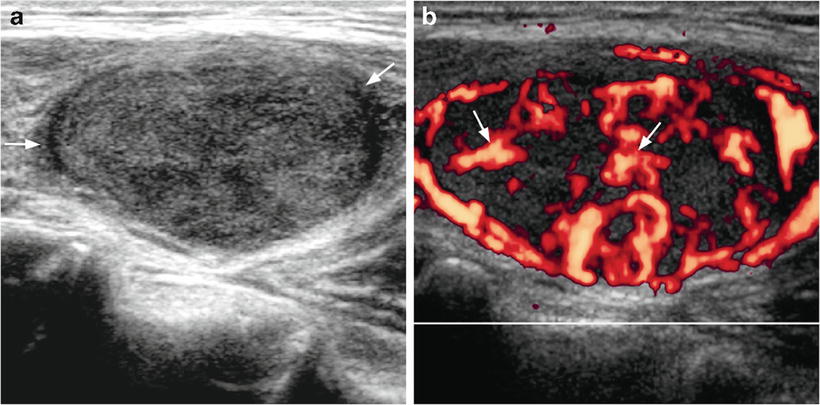

Colon Cancer Ultrasound Radiology Case Radiopaedia Org from prod-images-static.radiopaedia.org To see whether the cancer has spread, some or all of the lymph nodes are removed and checked for cancerous cells. We prospectively studied 19 patients referred to the institut gustave. It can be used with a fine needle aspiration test or core biopsy test to accurately direct the tip of the needle into the lump. If this lump is of concern then a biopsy would be the next step. They deliver blood from your heart to your brain. Head and neck cancers include cancers in: However, an ultrasound can tell if a lymph node has an abnormal architecture possibly because it is infiltrated by tumor. Sonography, when performed by an experienced examiner, can be used for evaluation of many pathologies in the head and neck area.

An ultrasound of the thyroid produces pictures of the thyroid gland and the adjacent structures in the neck. The scan is painless and only takes a few minutes. It can detect abnormal tissues, growths, and cysts and give a suspicion of cancer based on how those images look. Confirming that a lump in the neck is developing from the thyroid or connected tissue. Doctors and pathologists do not use internal ultrasound scan frequently to detect lymphoma. Ultrasound guidance is used to perform thyroid biopsies and improves the diagnostic accuracy of fine needle biopsy. The first lymph node cancer cells spread to is known as the sentinel node. Ultrasounds can't show lung cancer or bone cancer. Some of the indications for thyroid or neck ultrasound are thyroid nodules, goiter, thyroid cancer and other neck masses. For neck or thyroid mass see ent. To see whether the cancer has spread, some or all of the lymph nodes are removed and checked for cancerous cells. Fna might also be used in patients whose cancer has been treated by surgery and/or radiation therapy , to help find out if a neck mass in the treated area is scar tissue or if it's a return (recurrence) of the cancer. The lymph nodes in the neck are often the first place cancer cells spread to outside the primary site.

While it can't diagnose cancer, it can detect the abnormal tissues that may possibly be cancerous. Ultrasound is often one of the first line tests in the detection of cancer. For neck or thyroid mass see ent. Lymph nodes are part of the lymphatic system, which helps to protect us from infection and disease. Some of the indications for thyroid or neck ultrasound are thyroid nodules, goiter, thyroid cancer and other neck masses. Ultrasound imaging is a noninvasive medical test that helps physicians diagnose and treat medical conditions. Part of the throat (cancers of the oropharynx and tonsils, nasopharynx and hypopharynx) the nose or sinuses (nasal and sinus cancer) the salivary glands. Ultrasound guidance is used to perform thyroid biopsies and improves the diagnostic accuracy of fine needle biopsy. Sonography has an accuracy rate of about … Fna might also be used in patients whose cancer has been treated by surgery and/or radiation therapy , to help find out if a neck mass in the treated area is scar tissue or if it's a return (recurrence) of the cancer. If the person has a lump in the neck, an fna can show if the mass is from cancer spread. It can be used with a fine needle aspiration test or core biopsy test to accurately direct the tip of the needle into the lump. It can detect abnormal tissues, growths, and cysts and give a suspicion of cancer based on how those images look.